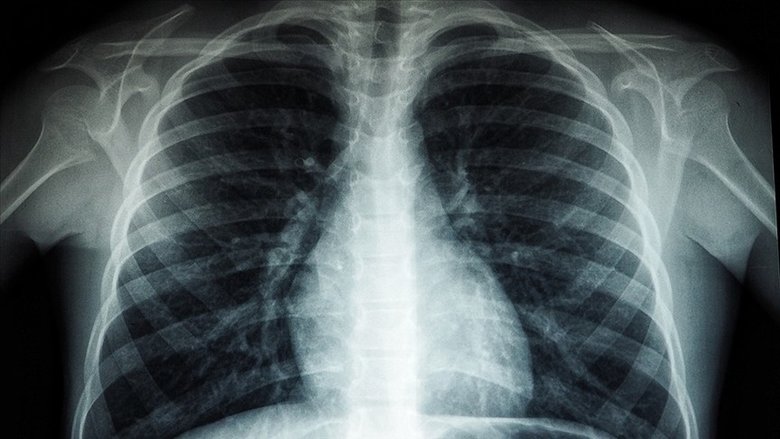

Multiple endokrin neoplazi tip 2 (MEN2), endokrin sistemde özellikle tiroit, paratiroit bezlerinde tümör oluşma ihtimalini artıran kalıtsal bir rahatsızlık olarak ifade ediliyor. Yüksek tansiyon, kilo kaybı, halsizlik veya yorgunluk, kemik kırılganlığı gibi belirtilerle kimi zaman kendini gösteren hastalık Iğdır'da yaşayan 30 yaşındaki Mahir Alagöz'de de tespit edildi. Uzun süre geçmeyen öksürüğü nedeniyle doktorlara gittiğini söyleyen, zaman zaman tansiyon problemi yaşayan Alagöz'e detaylı tetkikler yapıldı. Tetkiklerde kalsiyum değeri yüksek bulunurken taramalarında paratiroidde nodül, böbreküstü bezinde kalınlaşma, sağ akciğerinde yaygın büyük hava kistleri dışında sağ akciğer alt lobunu uzun süredir kapalı tutan bir tümör tespit edilerek MEN2 hastalığı bulunduğu belirlendi.

Tedavi sürecine yönelik bilgi veren Prof. Dr. Atinkaya Baytemir, "Endokrin ve diğer bölümlerle yaklaşık 3,5 aylık multidisipliner bir sürecimiz oldu. Çok titiz, özenli, aşama aşama hastada tedavi ve tetkik sürecini geçirdik. Hastadaki asıl problem; MEN dediğimiz genetik geçişli, ailesel bir sendrom olması. Hastamızın akciğerinde sadece alt parçadaki tümör değil bir de üst parçada çok büyük dev hava kisti dediğimiz kistleri mevcuttu. 30 yaşında bir erkek hasta, sağ akciğerin nerdeyse 4-5'te bir alana sahipti. Sağ akciğerdeki bu lezyonun olduğu hava yolunda sadece tümörlü alanı çıkardık, çıkardıktan sonra akciğerin cevabı da çok güzel oldu, açıldı. Hasta önemli bir akciğer kaybına uğramadı. Sigara kullanıyor, bırakmasını tavsiye ettik. Dünyada 35 binde bir görülen bir hastalık MEN2 Sendromu diye geçiyor, çok nadir bir hastalık. Multidisipliner yaklaşılması çok önemli. Son derece ender bir sendrom. Ömür boyu takip edilecek, kötü huylu bir tümör çıkmadı. Çıkan bütün lezyonlar iyi huylu. Hastamızın sağlıklı bir yaşam sürdürmesini bekliyoruz. 15 ila 30 yaş arasında genellikle semptomlar görülmeye başlıyor. Hasta önemsemezse tansiyon şikayeti, kan tükürme, sigara içmeye devam eder ama bununla ilgili bir kontrole gelmezse atlanabilir" dedi.